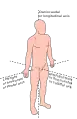

Standard anatomical position

Because animals can change orientation with respect to their environment, and because appendages like limbs and tentacles can change position with respect to the main body, terms to describe position need to refer to an animal when it is in its standard anatomical position.[1] This means descriptions as if the organism is in its standard anatomical position, even when the organism in question has appendages in another position. This helps avoid confusion in terminology when referring to the same organism in different postures.[1] In humans, this refers to the body in a standing position with arms at the side and palms facing forward, with thumbs out and to the sides.[2][1]

The axes of the body are lines drawn about which an organism is roughly symmetrical.[7] To do this, distinct ends of an organism are chosen, and the axis is named according to those directions. An organism that is symmetrical on both sides has three main axes that intersect at right angles.[3] An organism that is round or not symmetrical may have different axes.[3] Example axes are:

Examples of axes in specific animals are shown below.

Anatomical axes in a human, similar for other orthograde bipedal vertebrates

Anatomical axes in a human, similar for other orthograde bipedal vertebrates Anatomical axes and directions in a fish